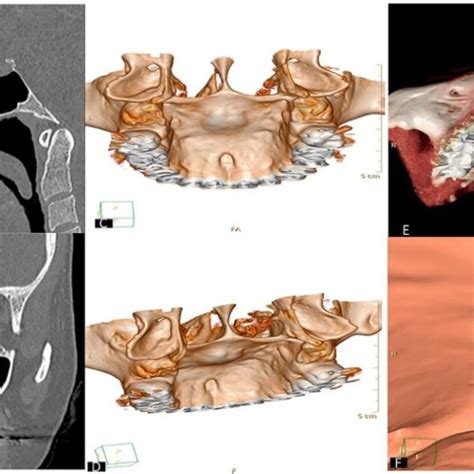

- Torus Palatinus: El torus palatinus es una protuberancia ósea benigna que se desarrolla en el centro del paladar duro. La genética suele estar detrás de este tipo de afecciones. El torus palatino es una afección poco frecuente, que se explica por la formación de un bulto de hueso en el paladar.

Ante la presencia de un bulto en el paladar hay que establecer un diagnóstico efectivo y de calidad. Para ello, nuestros especialistas abogan por llevar a cabo una completa exploración bucodental. Ortopantomografía para contar con una visión panorámica de toda la situación.